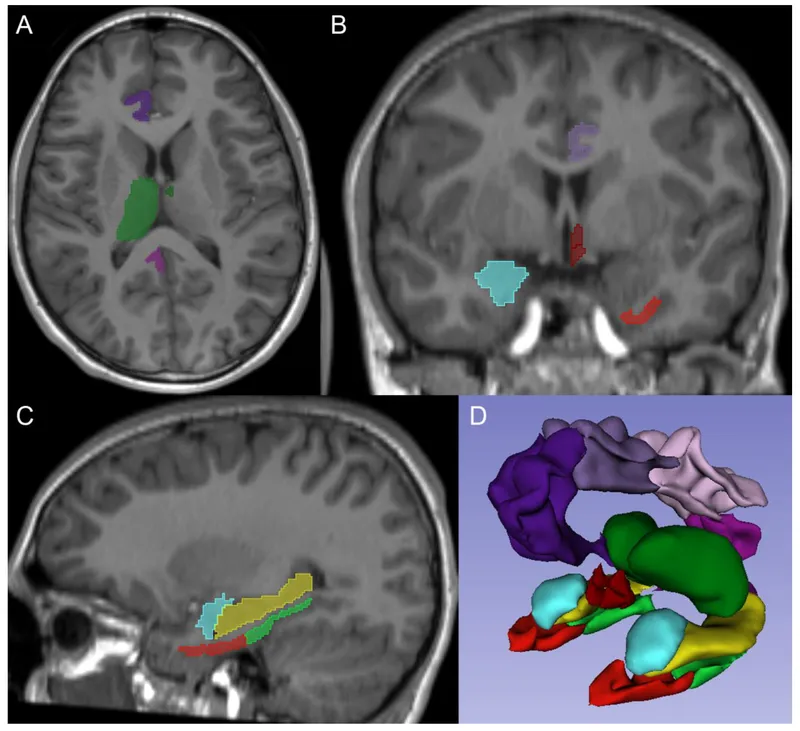

Limbic System - The Emotional Core

- Interconnected deep brain structures critical for emotion, memory, learning, and motivation.

- Key Components & Primary Functions:

- Amygdala: Processes fear, anxiety, aggression; key for emotional learning & memory (e.g., fear conditioning).

- Hippocampus: Essential for forming new declarative memories (short-term to long-term consolidation); spatial navigation.

- Cingulate Gyrus: Involved in emotional regulation, pain perception, motivation, and error detection.

- Fornix: Major output tract of the hippocampus, connecting it to mammillary bodies and septal nuclei.

- Mammillary Bodies: Relay for memory signals (part of Papez circuit).

- Papez Circuit: (Hippocampus → Fornix → Mammillary bodies → Anterior thalamic nucleus → Cingulate gyrus → Hippocampus) crucial for memory consolidation and emotional expression.